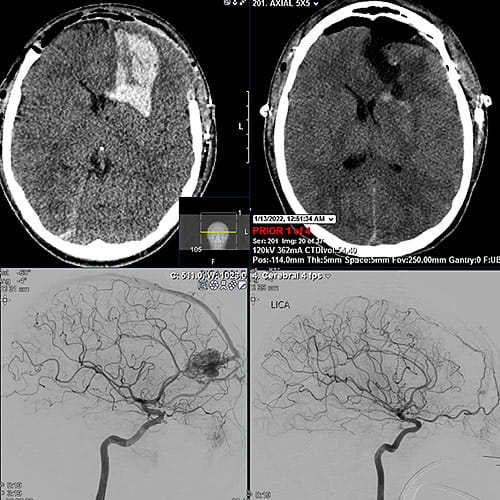

Convulsing in spasms, he was taken by paramedics to Southwest General Health Center, the closest hospital to his Columbia Station home. A CT scan of his brain showed a ruptured AVM, and a medical helicopter was called to transport Joshua to UH Rainbow, where a team of fellowship-trained pediatric neurosurgeons were waiting.

Joshua’s ruptured AVM occurred in his left frontal lobe, the section of brain that largely controls language and cognition. Dr. Tomei had to remove the front part of his skull to operate on the blood clot. The skull is left off for several days to prevent further injury when his brain swells during recovery in the Pediatric Intensive Care Unit.

Once Joshua recovered from the initial brain surgery, neurosurgeon Yin Hu, MD, performed an angiogram to essentially inject a glue-like material into the primary blood vessel feeding blood into the AVM. Then a third neurosurgeon, Abhishek Ray, MD, removed the AVM and replaced the skull a week later.